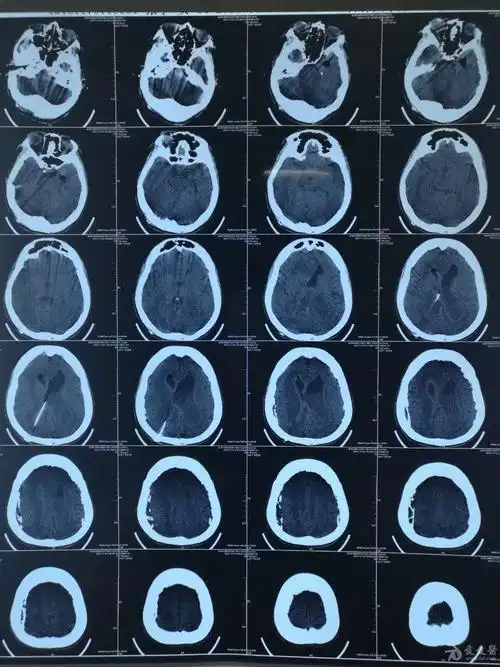

手术后可以明显改善症状,效果明显.脑积水ct显示:侧脑室,三脑室扩大

脑积水ct显示:侧脑室,三脑室扩大有症状的脑积水应该及时手术治疗.